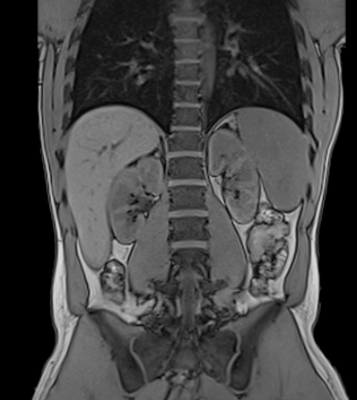

Why may we use an MRI to image the abdomen?